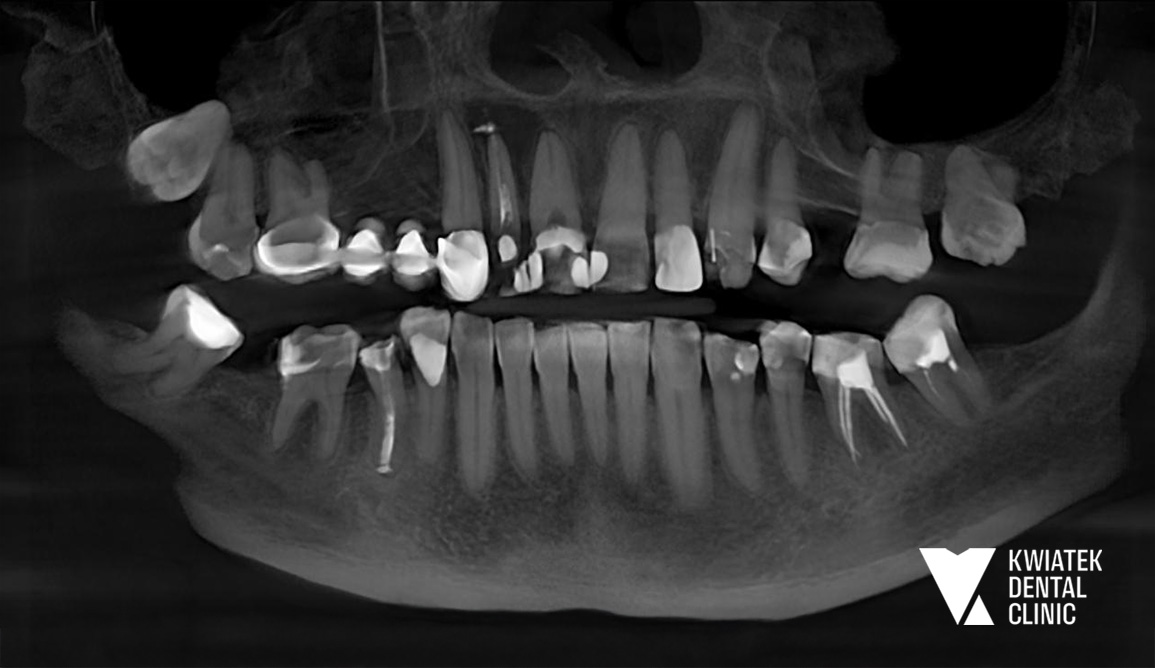

Pacjentka zgłosiła się do naszej kliniki z powodu silnych dolegliwości bólowych w obrębie przedniego odcinka szczęki. Leczenie kanałowe jednego z zębów było wcześniej rozpoczęte w innym gabinecie, jednak pomimo kilku wizyt dolegliwości nie ustępowały. W trakcie konsultacji klinicznej stwierdzono bolesność zębów, ich zwiększoną ruchomość oraz objawy wskazujące na proces zapalny w tkankach okołowierzchołkowych. Ze względu na złożoność problemu podjęto decyzję o przeprowadzeniu pełnej diagnostyki oraz zaplanowaniu kompleksowego leczenia.

W celu dokładnej oceny stanu tkanek wykonano badanie tomografii komputerowej CBCT. Badanie wykazało obecność zmiany zapalnej w kości podniebienia w okolicy zębów przednich, o wymiarach około 13 × 10 mm, co wskazywało na torbiel zębopochodną wymagającą leczenia chirurgicznego.

Podczas badania stomatologicznego stwierdzono również szereg dodatkowych problemów:

• nieszczelny most protetyczny w odcinku bocznym szczęki

• zaburzoną płaszczyznę zwarcia

• rotacje zębów oraz ich nieprawidłowe nachylenie

• znaczne starcie powierzchni zębów

• liczne ubytki próchnicowe i nieszczelne wypełnienia